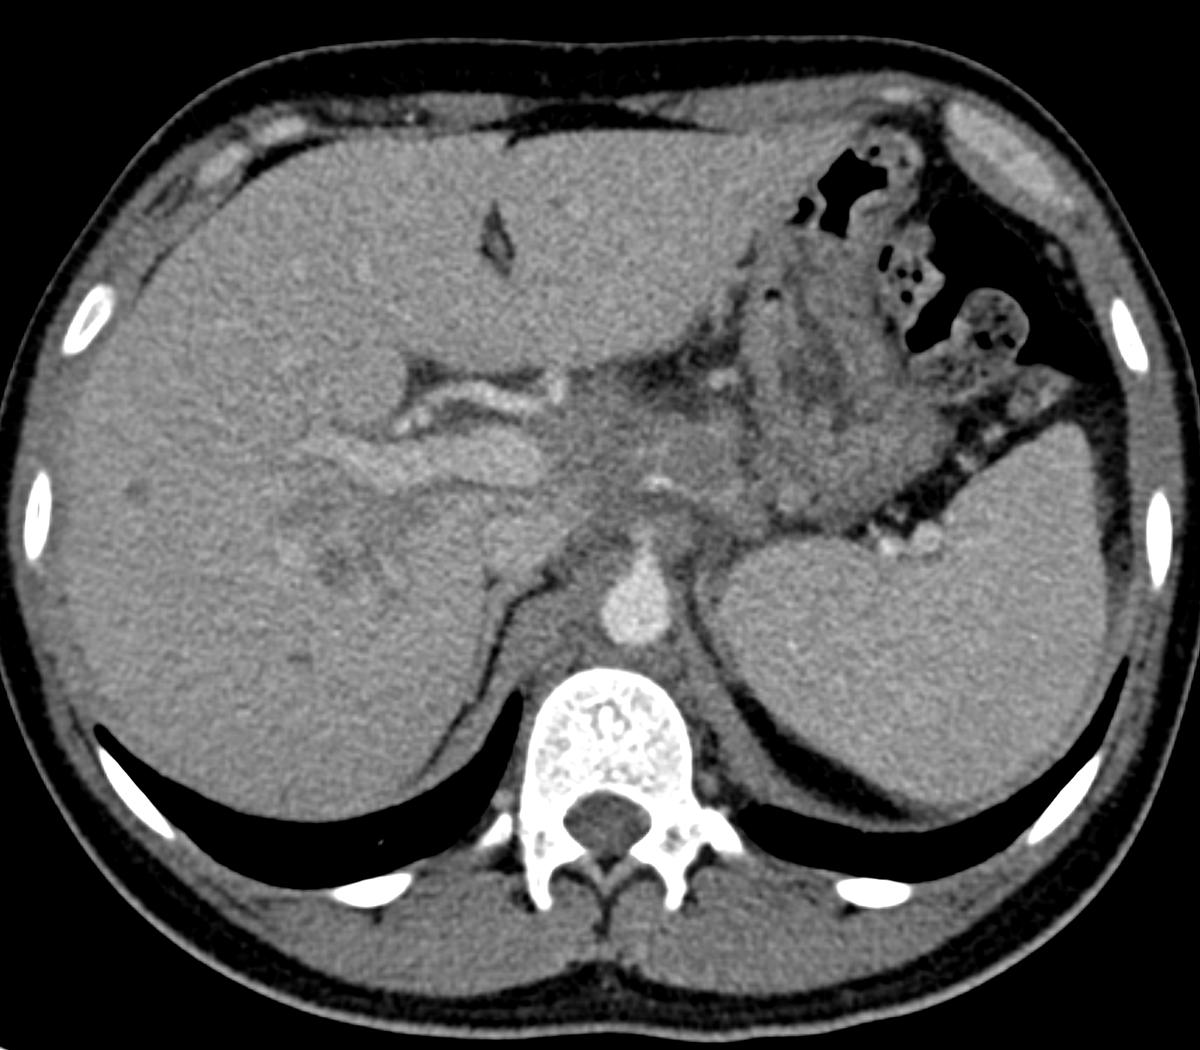

If you're having trouble choosing between an extracellular or hepatobiliary contrast agent for liver MRI, why not both? Read about the indications, protocol, and utility of dual-contrast liver MRI, now available in @RadioGraphics at pubs.rsna.org/doi/10.1148/rg…